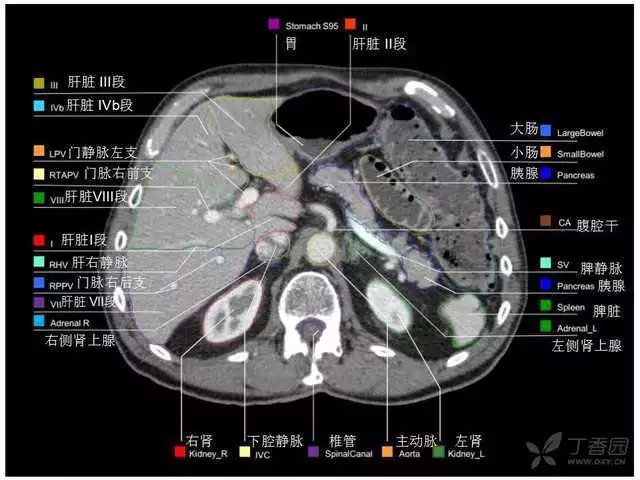

腹部肝脏高清CT断层的图谱

全腹部高清CT图谱,淋巴结彩色图谱,血管解剖图谱大汇总!

超声肝脏分叶及分段

肝脏分段和基本解剖学标志